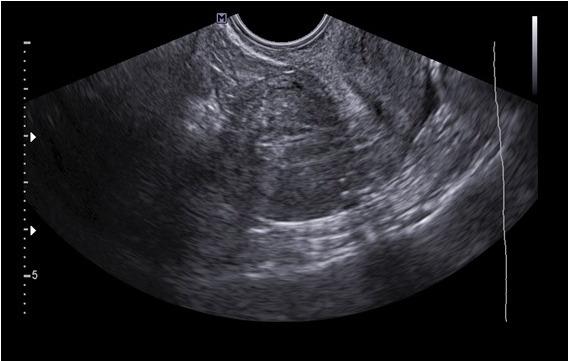

Three patients aged 16-30 years old presented with chronic pelvic pain [2016 - 2019]. Hormonal treatment failed in two cases. Cystic lesions in the myometrium (n=2), and the broad ligament (n=1) was detected on transvaginal 2D ultrasound (TV 2D US) and/or magnetic resonance imaging (MRI). The cyst was separate from the endometrium in all the cases, within the myometrium in two patients and in the right broad ligament in one case. The cystic lesions were confirmed on laparoscopy; and laparoscopic excision of the cysts with adequate repair of the myometrial beds were performed in all cases with fertility preservation. Robotic assistance was chosen in one case in an attempt to avoid injury of the fallopian tube based on the cyst location during a previous laparoscopy. The endometrial cavity was entered in one case.

Pathology report confirmed the diagnosis of JCA is all cases. There were no intraoperative complications. All three patients reported relief of their symptoms 6 to 8 months after surgery. No recurrence of the JCA was reported using TV 2D US in all cases.

2016年至2019年,3例年龄在16至30岁的患者出现慢性盆腔疼痛。2例激素治疗失败。经阴道二维超声(TV 2D US)和/或磁共振成像(MRI)检测到肌层囊肿(n = 2)和阔韧带囊肿(n = 1)。所有病例中囊肿均与子宫内膜分离,2例位于肌层,1例位于右侧阔韧带。腹腔镜检查证实了囊肿病变;所有病例均进行了腹腔镜囊肿切除术,并对肌层床进行了适当修复,以保留生育能力。其中1例选择了机器人辅助手术,试图根据先前腹腔镜检查时囊肿的位置避免损伤输卵管。1例进入了子宫内膜腔。

病理报告证实所有病例均诊断为JCA。术中无并发症。所有3例患者术后6至8个月均报告症状缓解。所有病例经TV 2D US检查均未报告JCA复发。